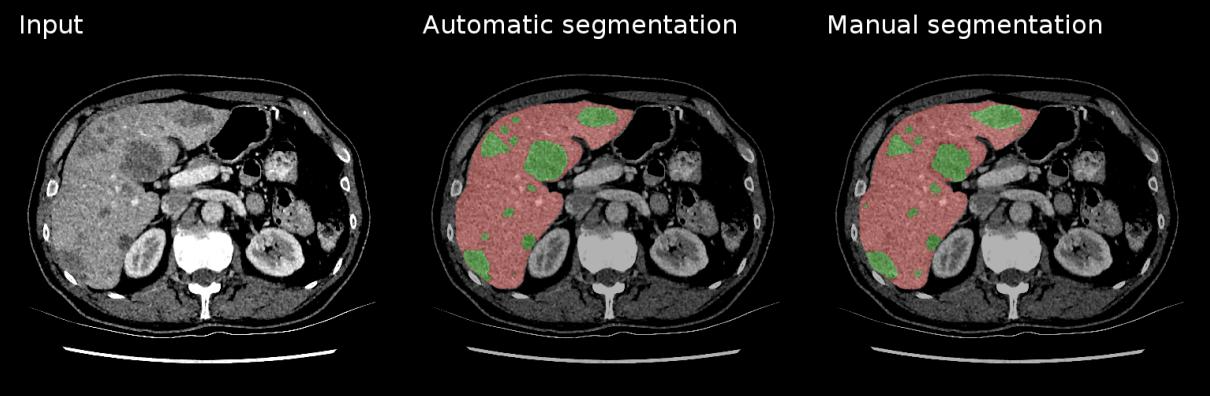

Image Segmentation

Segmentation is the most detailed form of visual understanding — it classifies every pixel in an image. Instead of one label per image (classification) or boxes around objects (detection), segmentation produces a mask that precisely outlines each region of interest. This matters clinically: a bounding box around a tumor tells you roughly where it is, but a segmentation mask tells you its exact shape, volume, and boundaries — critical for surgical planning and radiation therapy.

U-Net Architecture

U-Net (Ronneberger et al., 2015) was designed specifically for biomedical image segmentation and remains the dominant architecture for medical imaging. It works remarkably well even with very limited training data.

tl;dr — U-Net uses a U-shaped encoder-decoder CNN. The encoder extracts features at increasing granularity using convolutions and pooling. The decoder upsamples these features back to the original image size. Skip connections link encoder features to the decoder, combining “what” (semantic context) with “where” (spatial detail) for precise segmentation.

Loss Functions for Segmentation

Standard cross-entropy works but struggles with the extreme class imbalance common in medical segmentation (e.g., a small tumor in a large image). Specialized losses like Dice Loss optimize overlap directly, making them less sensitive to imbalance.